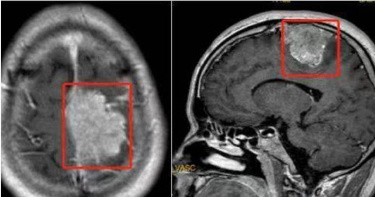

65歲吳小姐最近幾年來,時常感覺頭痛、頭暈與視力模糊,到眼科診所檢查結果為眼壓過高,再接受眼科診所建議去大型醫院檢查後,才偶然發現右側前額葉有一顆直徑9公分的巨大腦膜瘤,決定至醫院腦神經外科求診。醫師預估半年內極有可能會導致昏迷死亡,緊急動手術解除這個腦中的「不定時炸彈」救回一命。顱內壓升高 短時間恐昏迷死亡大里仁愛醫院腦神經外科張育銘醫師表示,吳小姐求診時已經出現「顱內壓升高」的症狀,包含頭痛、頭暈和眼壓升高等,後續核磁共振影像亦發現因為腫瘤壓迫使得旁邊的腦組織開始出現水腫的情況,有可能再過三個月至半年就會因為壓力升高造成昏迷而死亡。後來幸虧即時安排手術處理,手術中使用精密顯微鏡、導航系統與神經監測系統,小心地將腫瘤完全切除,病人順利地恢復健康,也沒有出現任何神經後遺症。九成腦膜瘤為良性 生長緩慢難察覺張育銘醫師指出,腦膜瘤是顱內最常見的原發性腫瘤,一般來說,九成的腦膜瘤為良性,生長速度緩慢。因此,腫瘤在生長過程之中往往難以察覺,除了有少數病人是在偶然中發現腫瘤的,大多數病人都是等到有神經壓迫症狀或顱內壓升高時才被診斷出來;除了上述提到的症狀之外,也會出現癲癇、肢體麻木無力或口齒不清等較少見的情況。女性比男性易發生 這1情況能追蹤觀察即可吳小姐因為出現顱內壓升高的情況,才需要施以「開顱腦瘤切除手術」將腫瘤切除,後續的病理報告發現是「非典型腦膜瘤」,為世界衛生組織分類第二級(WHO grade II),其分化程度介於良性與惡性之間,發生率較少,需要後續放射治療。張育銘醫師說,依據腦膜瘤的研究認為其成因可能與女性荷爾蒙的黃體激素有關係,女性比男性容易發生,比率大約為2:1,如果發現腦膜瘤時直徑不大,而且沒有影響到神經功能的話,其實也是可以選擇追蹤觀察。持續性出現這些症狀 應盡快就醫張育銘醫師呼籲,如果有出現「持續性」的頭痛、頭暈、噁心嘔吐或視力模糊等症狀,可至門診尋求醫師詳細的問診與理學檢查,若有必要會安排後續的影像檢查以釐清病情。

本來整日都神采奕奕的58歲邱女士日前突然變得疲倦消極,以為自己是身心方面出了狀況,故而至台北慈濟醫院身心醫學科門診。醫師問診後發現,邱女出現步行不穩、視力模糊、嗅覺喪失等症狀,便安排核磁共振造影,結果顯示患者前顱底有一顆8公分的巨大腦瘤,遂轉診至神經外科門診。李定洲醫師予以腦瘤全切手術,成功摘除巨大腦膜瘤,1週後平安出院。李定洲醫師指出,腦膜瘤的發生率佔整體腦瘤的三分之一,尤其好發於30歲至50歲成人,其中以女性居多,男女比約1:2。腦膜共有三層,由外到內依序是硬腦膜、蜘蛛網膜及軟腦膜,腦膜瘤的成因主要來自蜘蛛網膜的帽狀細胞增生,常生長於大腦半球的圓凸部、蝶谷脊、矢狀竇旁等部位。醫師說明,大多數腦膜瘤生長速度緩慢,出現的症狀取決於其生長位置與速度,以邱女士為例,前顱底由額骨的框板、蝶谷體前部、蝶谷小翼和篩骨的篩板構成,容納大腦半球的額葉,額葉掌控人體的自主行為,如負責行走行為、視覺感知、長期記憶與情緒控制,一旦腦膜瘤生長於前顱底,便會造成額葉損傷,因而出現頭暈頭痛、噁心嘔吐、嗅覺喪失、視力減退、情緒變化等臨床表徵。李定洲醫師提醒,若是出現劇烈頭痛及神經功能異常時,務必及時就醫。(圖/台北慈濟醫院提供)李定洲表示,腦膜瘤的治療以腦瘤全切手術為準則,透過高速氣鋸打開適當大小的頭骨將腦膜瘤剝離後取出,但開顱手術仍會存在無法完整摘除的可能,因此可採用立體定位放射治療,藉由三度空間立體定位的方法將多個放射線射束集中於顱內病灶,以發揮定點、聚焦的治療效果,亦能避免周邊正常組織受到不必要的照射。李定洲醫師提醒,若是出現劇烈頭痛及神經功能異常時,務必及時就醫;同時也建議具有家族史或神經學症狀異常的40歲以上成人定期接受核磁共振造影或電腦斷層檢查,從而早期發現、早期治療。